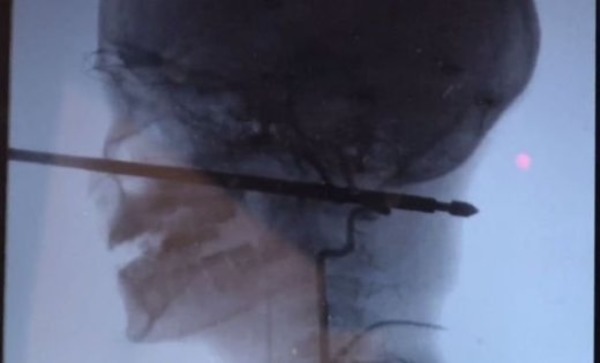

Мальчик играл в доме, закрепленном на стволах деревьев, когда на него напали осы. Он свалился с высоты чуть более метра и приземлился прямо на 30-сантиметровый металлический шампур для приготовления шашлыков. Шампур пронзил череп и погрузился в ткани головы на 15 сантиметров. К счастью, чудесным образом металлическая палка вошла в голову, миновав и глаза, и мозг, и спинной мозг, и крупные кровеносные сосуды.

Так как из раны не было активного кровотечения и шампур не повредил жизненно важные органы, врачи успешно удалили квадратный стержень. Операция была очень сложной именно из-за формы шампура с острыми краями и длилась несколько часов.

Коджи Эберсоул, директор отделения эндоваскулярной нейрохирургии больницы Университета Канзаса сказал Kansas City Star, что самую большую сложность для хирургов при удалении шампура представляли кровеносные сосуды на шее мальчика. Врач назвал чудом то, чтобы при такой сквозной травме шампур не повредил ничего в голове потерпевшего роковым образом.